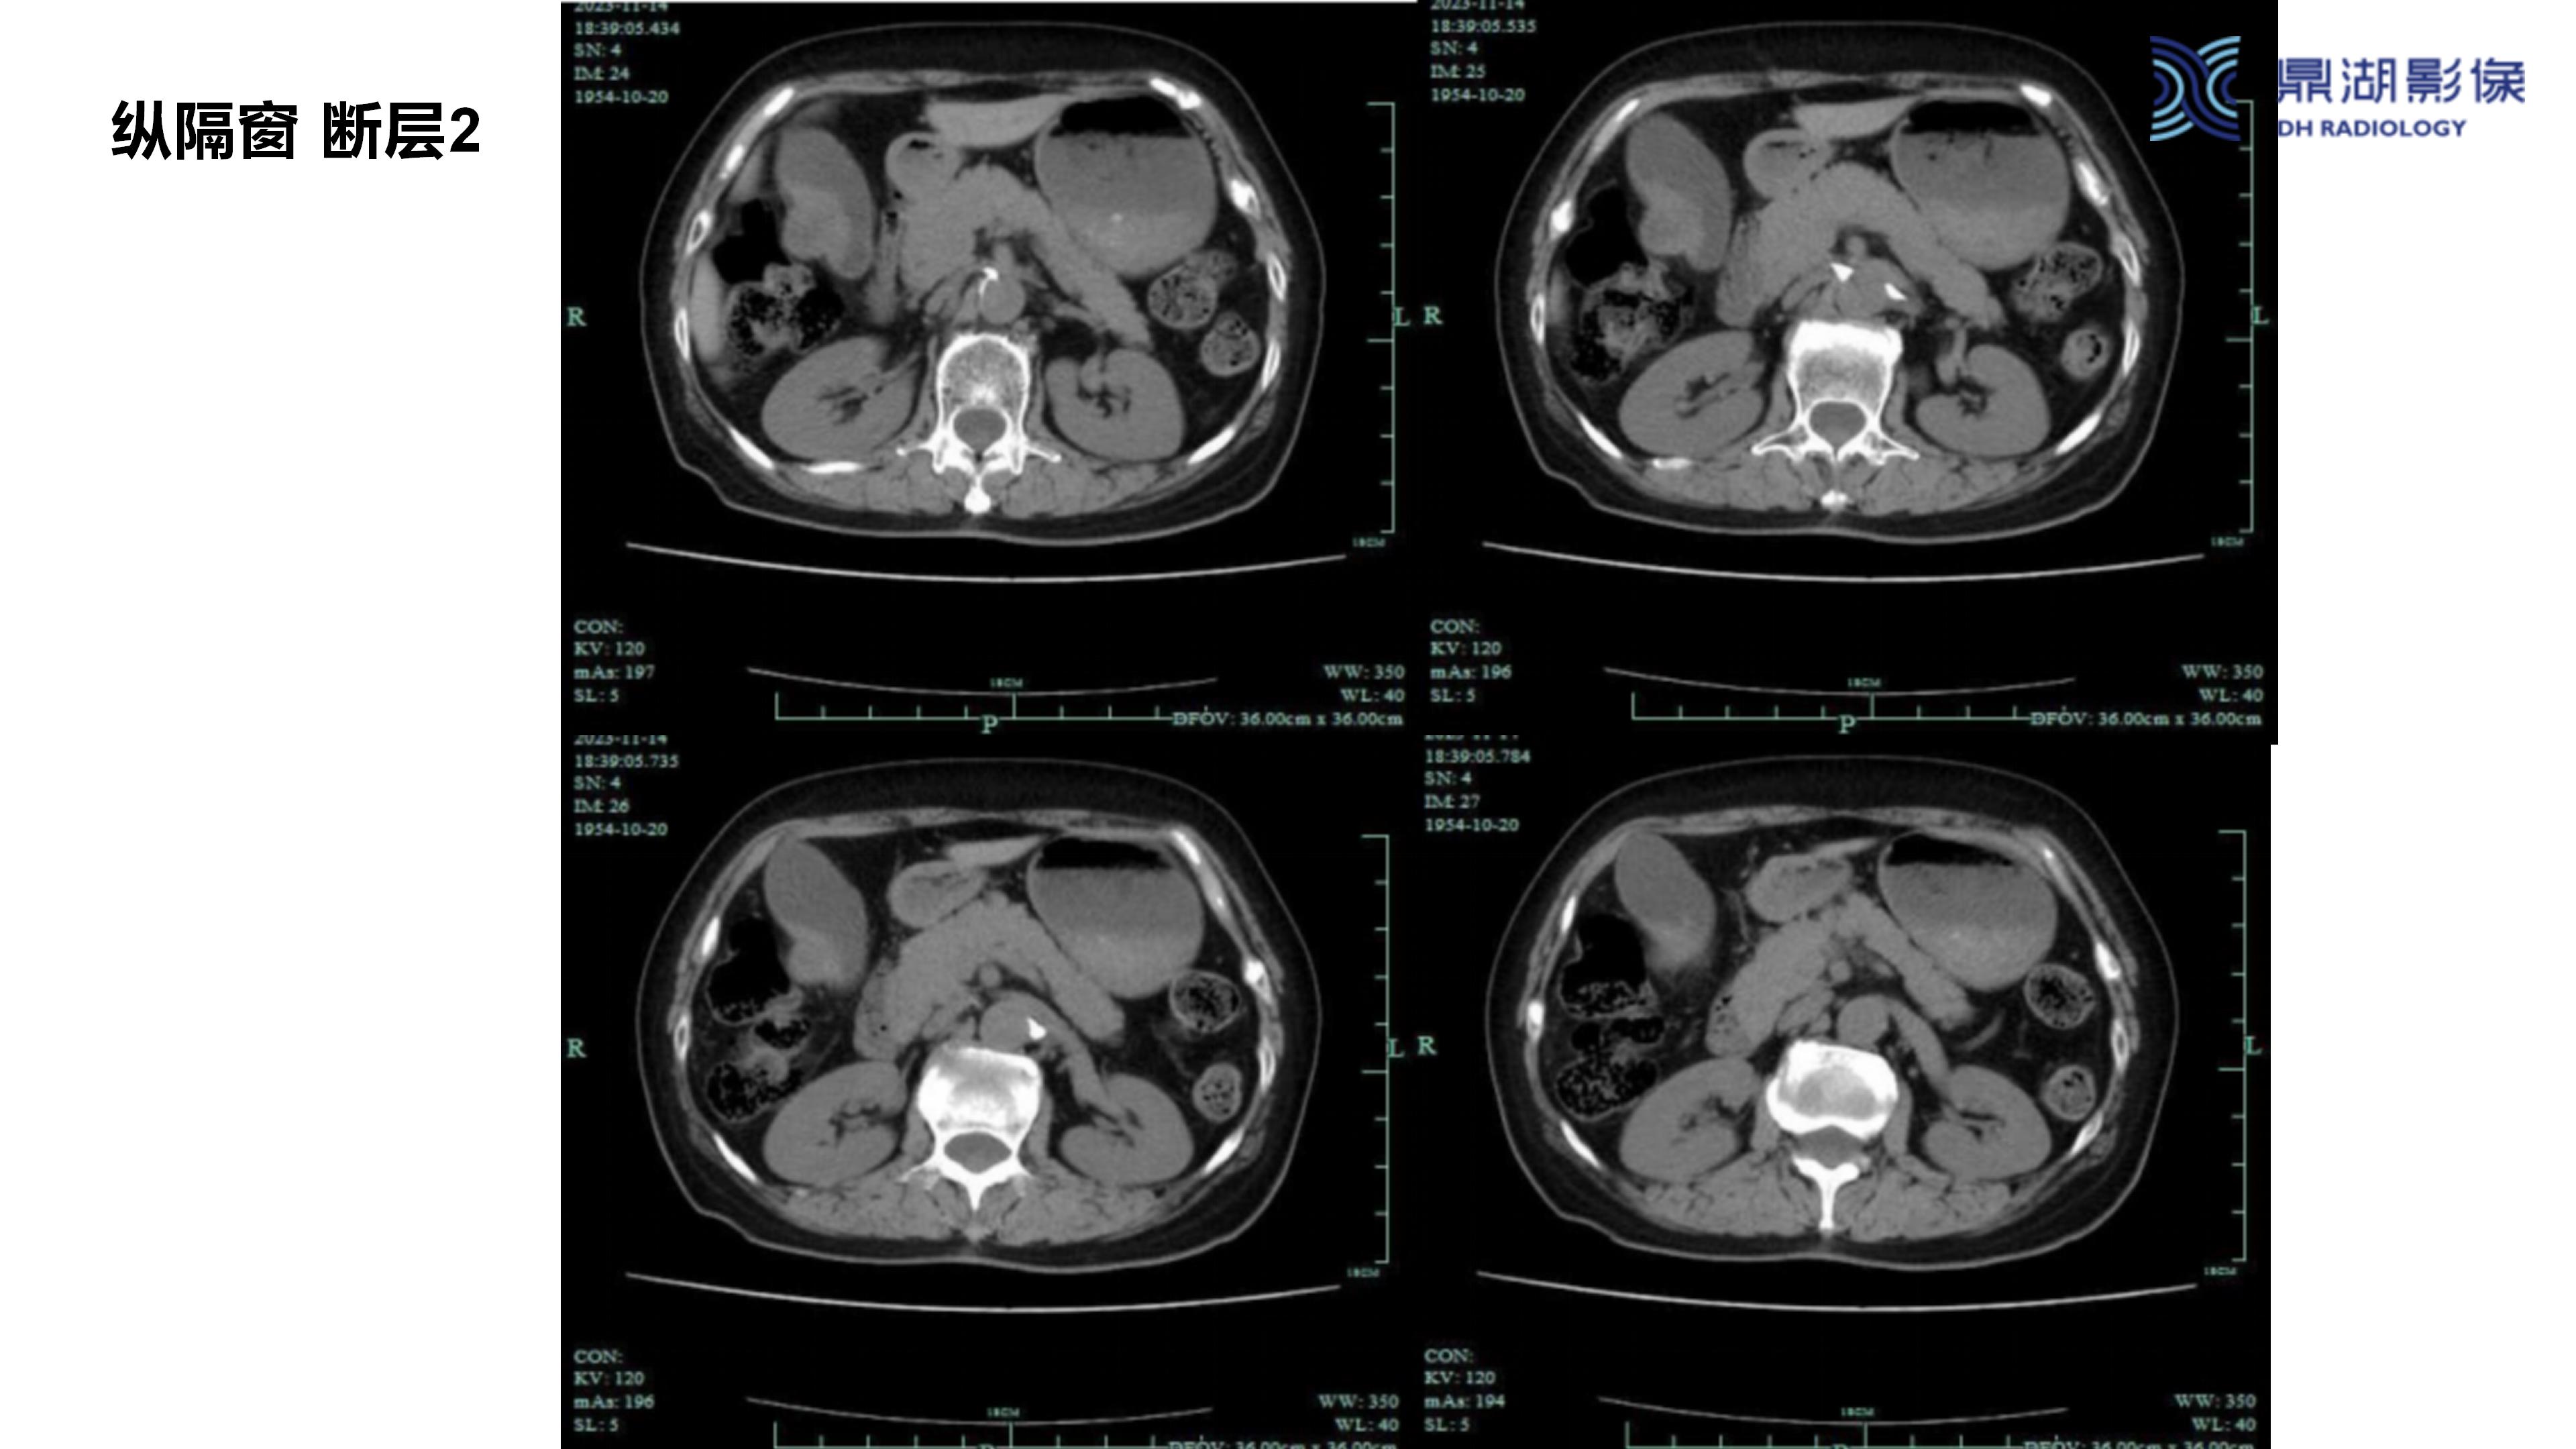

胆囊癌-鼎湖社群读片病例